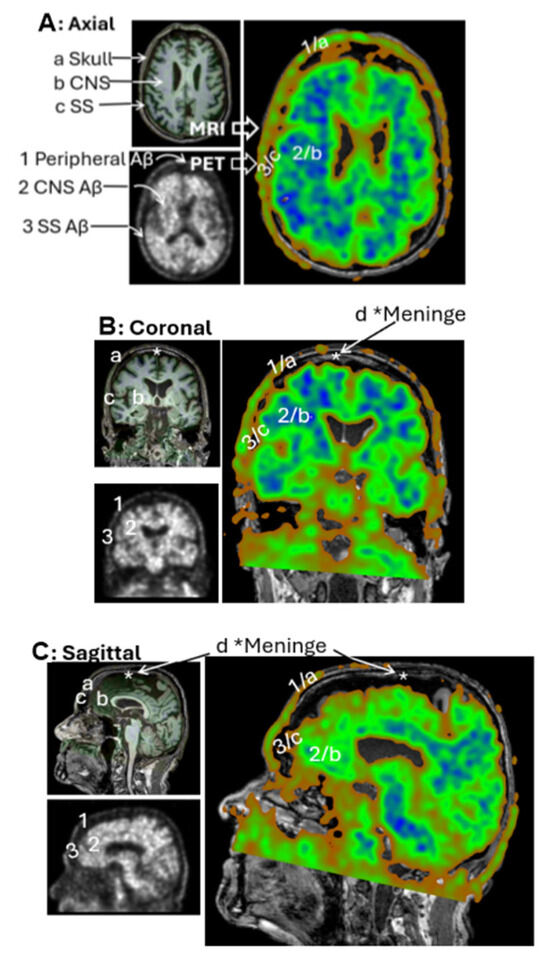

The individual slice thickness in florbetapir PET scans is 2.0 mm, displaying as gray signals against the black background. At this resolution, the intensity of Aβ signals is often low and appears blurred to the human eye. To improve the analysis of the Aβ signal, we reconstructed these slices into a 3D volumetric image, enabling to gather more signals from regions of interest (ROIs) across multiple spatial dimensions. Figure 1A illustrates the transformation from 2D slices to a compact 3D volume encompassing the brain, skull, and portions of the cervical region. However, this initial 3D reconstruction was suboptimal for analysis and required further processing.

In the original PET images, Aβ concentrations were represented by grayscale pixel values ranging from 0 (black; no Aβ) to 255 (white; highest Aβ concentration). Following 3D reconstruction, these 2D pixels were converted into 3D voxels, each assigned to a color based on an arbitrary intensity scale (Figure 1B). In this study, voxel intensities were visualized using a color gradient: green for the lowest Aβ levels, yellow to brown for intermediate levels, and red for the highest concentrations.

To refine the imaging, we applied convolutional neural networks (CNNs) to filter out noise associated with positron straying far from radioligand binding sites, while enhancing signals proximal to ligand interactions. This CNN-based process significantly improved image clarity and reduced blurring. We found that using three consecutive slices was sufficient to produce a clear and interpretable image (Figure 1C). However, when more than ten slices were combined, the resulting visualization became overly complex, obscuring individual anatomical features. Interestingly, Aβ signals were detected not only within the brain parenchyma but also in peripheral regions, including the skull and cervical areas. Notably, Aβ concentrations appeared homogeneous in the skull but heterogeneous in the cervical region, suggesting a broader anatomical distribution and potentially dynamic clearance pathways beyond the central nervous system.

Figure 1. Three-dimensional Reconstruction for Florbetapir PET Imaging. (A), General workflow for generating a 3D volume from PET data. A total of 346 individual slices were synthesized into a single 3D image. The imaging data were obtained from the CU-1 individual (see Table 1 in Section 2) and used here as a representative demonstration. (B), Voxel-based color mapping of Aβ concentration following 3D reconstruction. Original PET grayscale values (ranging from 0 [black; no Aβ] to 255 [bright; highest Aβ]) were converted into voxel intensities and visualized using a color gradient: green () for the lowest Aβ levels, yellow-brown for intermediate levels (), and red for the highest concentrations (). (C), Comparison between raw PET imaging (top panel) and 3D reconstruction (bottom panel). The 3D reconstruction significantly improved image clarity, with optimal visualization achieved using three slices of 6.0 mm thickness.